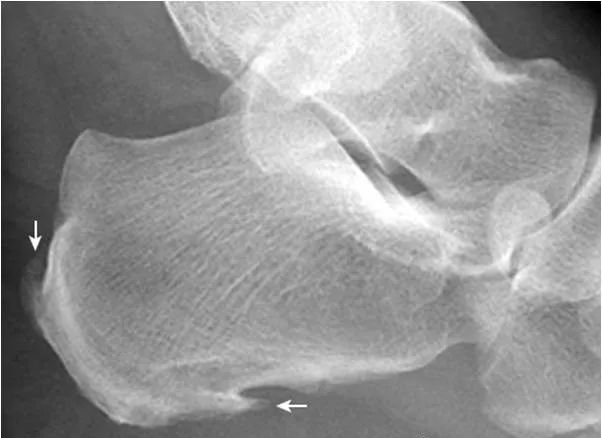

1.跟骨结节骨骺:

形态多样,密度致密(箭),伴裂隙(箭头),为正常表现,勿误认为坏死。

2.Haglund外生骨疣与不典型骨刺:

跟骨后上缘骨刺样突起(箭),属正常变异,称Haglund外生骨疣。穿高跟鞋时可损伤相邻的跟腱,形成Haglund综合征;跟骨结节下缘前突骨刺样突起(箭头),正常人可见,可无临床症状。